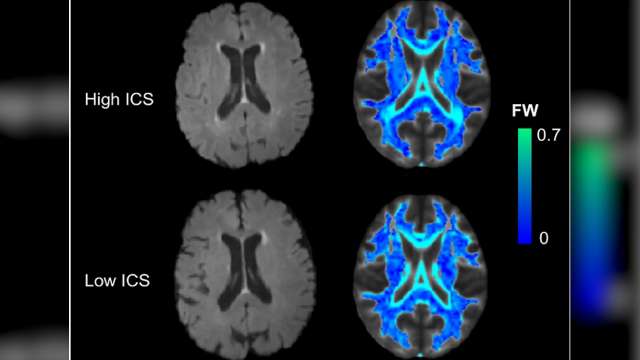

Dr. Jason Hinman's lab is focused on identifying the molecular pathways that interface the two most common neurologic disorders: stroke and dementia. The goal is to develop new diagnostic tools to better recognize patients who are at risk for post-stroke cognitive impairment and dementia, and develop treatments based on discoveries they've made in the lab.